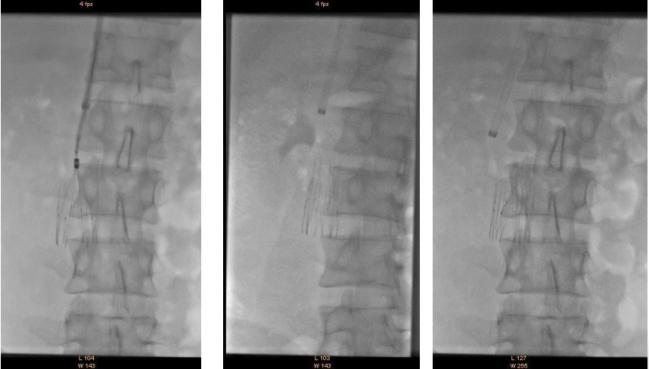

溶栓导管拔除前应做静脉造影,不仅可以判断溶栓效果,还可以发现和诊断髂静脉压迫综合征。髂静脉压迫综合征在正常人群中发生率约三分之一,在下肢深静脉血栓的病人中发生率较高。髂静脉压迫综合征一般发生在左侧,因为左侧髂静脉在生理上就位于右侧髂动脉和脊柱之间,很容易受压。这也是下肢深静脉血栓大多数发生在左侧下肢的原因。如果血栓没有完全溶解,且不准备接受髂静脉支架手术者,可以复查彩超后拔除导管。

在人体正常解剖结构中,腹主动脉 -左右髂动脉和下腔静脉-左右髂静脉并行,右侧髂动脉发出后跨在左侧髂静脉前方, 左侧髂静脉后方是脊柱与骶骨。这样,左侧髂静脉经常会受压 形成狭窄,估计约三分之一的人会出现明显狭窄,称为髂静脉 压迫综合征。在静脉造影中可以表现为不同程度的狭窄,严重 者为静脉闭塞。它是下肢深静脉血栓发生的重要危险因素之一,也会明显影响远期下肢静脉功能。